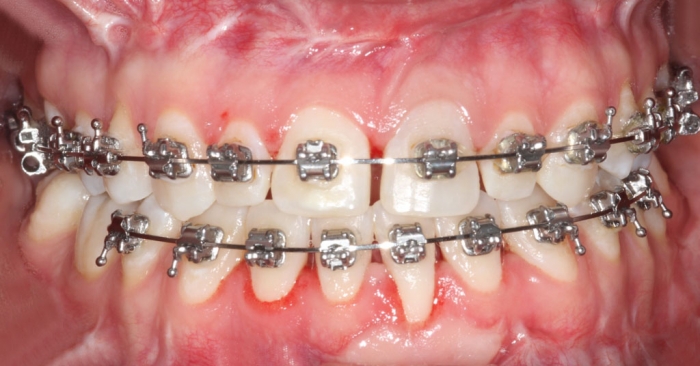

Mordida após a cirurgia - Clínica Cliniface

Mordida após a cirurgia